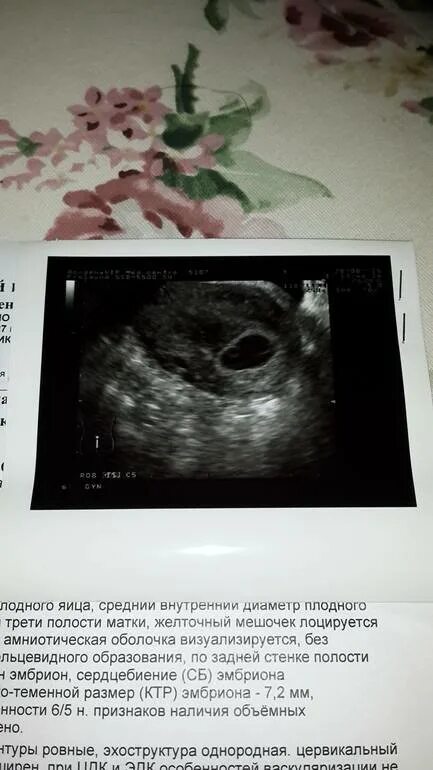

Плодное яйцо эмбрион не визуализируется